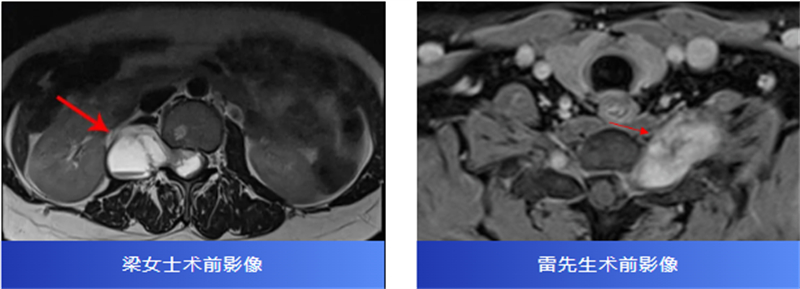

后来,经过腰椎磁共振检查,才发现原来是椎管内长了一个肿瘤,压迫着神经,并向外生长,延伸到了右肾附近,情况十分复杂。

两名患者转诊至柳州市人民医院后,脊柱外科主任、主任医师胡巍博士迅速组织医学影像科、麻醉科等多学科会诊。团队对肿瘤病变范围、与神经的毗邻关系进行周密评估,为每位患者制定个体化手术方案。

术中,在显微镜辅助下,医生精细分离肿瘤与神经组织,小心翼翼解除压迫,最终切除了肿瘤。病理报告也带来好消息:两人均为良性神经鞘瘤。

术后,梁女士的腰腿痛消失了,雷先生的颈肩胀痛也得到了缓解。两位患者都保住了正常的神经功能,步入康复的新阶段。